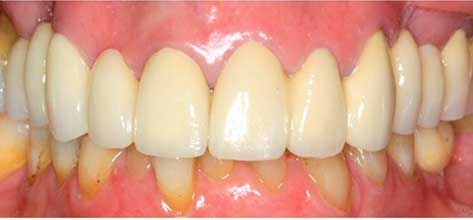

En la primera fotografía se observan coronas envejecidas, diferencias de color y desgaste generalizado. En el después se aprecia una restauración mucho más armónica, con coronas renovadas que mejoran la estética, la uniformidad y la función de la sonrisa.